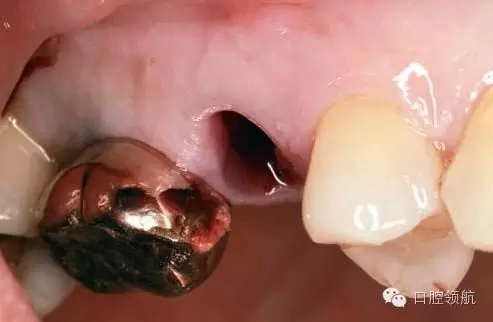

患者10年前,在外院于( 左上第六顆牙)區(qū)行上頜竇底提升術(shù)同期植入種植體,經(jīng)過10年上頜竇內(nèi)生成骨完全吸收消失了(圖1)?;颊叽舜蝸碓菏且?yàn)猷徰? 左上第五顆牙) 不能保存,希望行種植修復(fù)治療。

圖1 術(shù)前牙片。由于上頜竇底黏膜提升植骨術(shù)而在上頜竇內(nèi)生成的骨已完全消失。